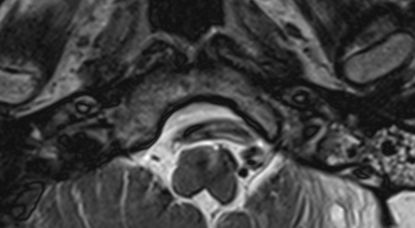

Εικόνα 1.1. Προεγχειρητική μαγνητική δεξαμενογραφία δείχνει το προσωπικό νεύρο να υφίσταται γωνίωση και πίεση από την στρεβλωμένη σπονδυλική αρτηρία πάνω στο οπίσθιο τοίχωμα του έσω ακουστικού πόρου.

Η μαγνητική τομογραφία έδειξε μεγάλη πίεση και γωνίωση του προσωπικού νεύρου απο μία δολιχοεκτατική (στρεβλωμένη και διογκωμένη) σπονδυλική αρτηρία, στο σημείο που το νεύρο εισέρχεται στον έσω ακουστικό πόρο. Το πρόβλημα δεν ελέγχετο με φάρμακα, και η ασθενής είχε ήδη υποβληθεί ανεπιτυχώς σε δύο επεμβάσεις στην γεφυροπαρεγκεφαλιδική γωνία, σε άλλες κλινικές. Η δεύτερη επέμβαση είχε γίνει στο International Neuroscience Institute, στο Αννόβερο, από τον διεθνώς αναγνωρισμένο καθηγητή Madjid Samii.